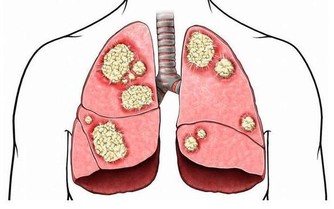

最近有這樣一則消息讓人痛心不已,一名17歲的女孩竟然被查出了胃癌,而且已經是晚期,據了解,女孩被確診的時候,就已經檢查出很大面積的胃潰瘍和不規則佔位性病變,癌細胞也已經擴散,向腹腔內肝門、腹膜、腸系膜、肝臟等部位侵襲,已到晚期。

早期胃癌患者基本是沒有症狀的,少數患者即使有症狀也是一些非典型性症狀,如食慾不振、腹部不適等,易被人誤認成胃炎、胃潰瘍等胃病,以致很多人選擇吃點小藥即可,導致一旦出現嚴重症狀時,被檢查出來的胃癌往往已經到了中晚期,如同該名女孩一樣。

有專家表示,胃癌可發生與任何年齡,發病率隨著年齡的增長而上升,一旦發現不舒服,如短時間內體重明顯下降、胃部以及上腹疼痛不適等,應儘早進行內鏡檢查,早發現、早診斷、早治療。切不可因對內鏡檢查手段畏懼,被動或主動地忽視了消化道腫瘤的早期篩查。